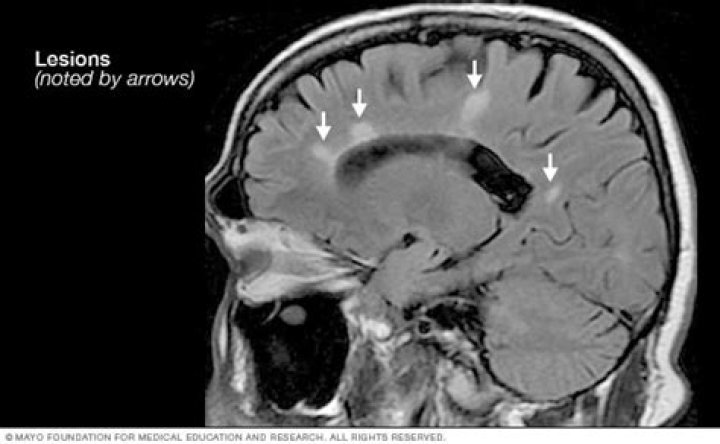

What is the McDonald criteria for MS diagnosis?

Under the McDonald Criteria (revised), an MS diagnosis is likely if myelin damage is disseminated in space, as seen in an MRI as: At least one T2 bright lesion in at least two or four CNS locations: the juxtacortical, perventricular and infratentorial areas of the brain, and the spinal cord.

Do MS lesions come and go?

“Paradoxically, we see that lesion volume goes up in the initial phases of the disease and then plateaus in the later stages,” Zivadinov says. “When the lesions decrease over time, it’s not because the patient lesions are healing but because many of these lesions are disappearing, turning into cerebrospinal fluid.”

Is CT or MRI better for MS?

Not only is MRI more sensitive than computerized tomography (CT/CAT scan) in picking up MS lesions it also does not involve radiation exposure as the images are generated by magnetic fields and radio waves.